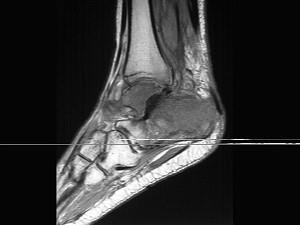

问题 男,28岁,踝部肿痛,结合图像,最可能的诊断是 ( ) .

选项 A、跟骨结核 B、踝关节类风湿关节炎 C、跟骨骨髓炎 D、踝关节滑膜炎 E、未见异常

答案 C